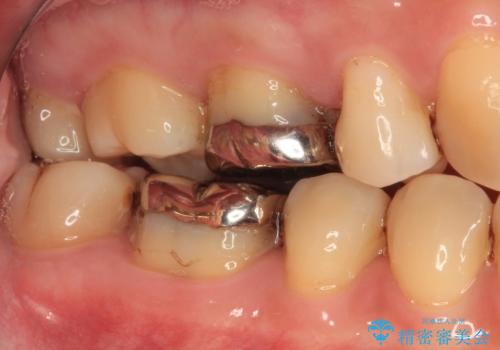

- 人と話す際に、下顎の奥にある銀歯が目立って気になるとのことで来院された患者様です。

左右の奥歯に銀歯のクラウンが装着されていたため、銀歯除去後に仮歯に置き換え、フルジルコニアクラウンにて補綴治療を行うこととしました。